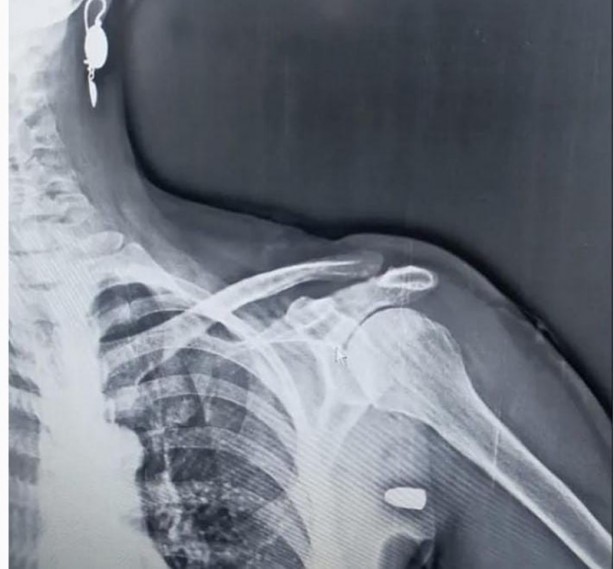

Trabzon-Tonya'da sol omzuna yorgun mermi isabet eden kadın neredeyse canından oluyordu.

İlçenin Karaağaç Mahallesi yakınlarındaki Hırsafa Yaylası’nda ot biçen Asiye İnce (59), önceki gün yayla evinin yanındaki bahçede ot biçerken sol omuz bölgesinden giren yorgun mermi ile yaralandı. İnce, yakınlarının yardımıyla Tonya Devlet Hastanesi'ne kaldırıldı

Burada yapılan müdahalenin ardından Vakfıkebir Devlet Hastanesi'ne sevk edilen İnce'nin omuzundaki mermi çekirdeği ameliyatla çıkartıldı. Asiye İnce hastaneden taburcu edilirken, başından geçenleri anlattı.

Asiye İnce'nin eşi Yakup İnce (61) ise "O gün bende hastanedeydim. Telefonum çaldı hayırdır dedim. Orda dur vuruldum geliyorum dedi. Şaşırdım kimseyle alıp veremediğim yok. Hastaneye geldiler kurşun şah damarına 1.5 santim kala girmiş. Kalbe yakın bir noktada girmiş. Silahın eğitimli kişilere verilmesini istiyorum. Eğitimsiz her önüne gelenin silah almamasını istiyorum. Yaylada hiç böyle bir şeye rastlamamıştık. Allah'ıma bin şükür eşimi bana bağışladı" dedi.